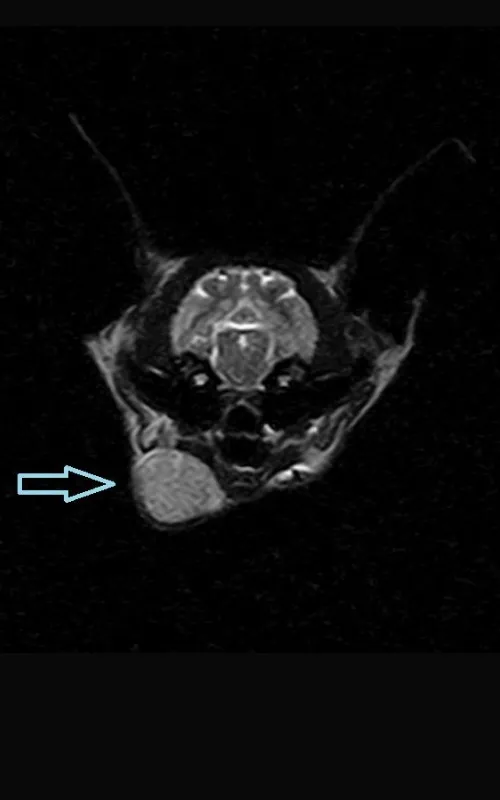

Under the care of Dr Wan Ju Jao, Lando had surgery to remove the affected lymph node and reduce the fungal burden. Testing of the tissue confirmed severe lymphadenitis caused by cryptococcosis, and a serum cryptococcal antigen test showed high levels. Analysis of his cerebrospinal fluid also confirmed the infection had reached his central nervous system.

Ultrasound result